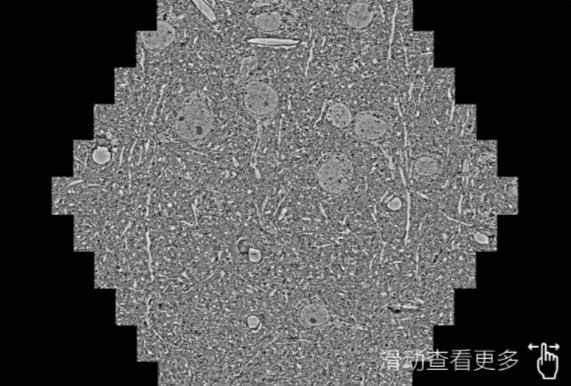

鼠脑切片。左图使用沈阳蔡司沈阳扫描电镜MultiSEM706对165μmx143pm面积区域成像,耗时仅需1.5秒。右图为鼠脑切片中30μm区域放大效果。样品由芝加哥大学B.Kasthuri提供。